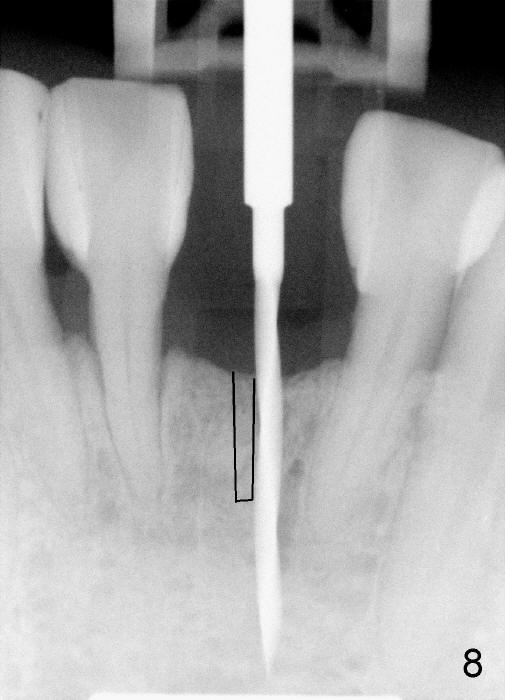

A 3x17 mm one piece implant is planned. Osteotomy is created by a 1.5 mm pilot drill at the depth of 14 mm without incision (Fig.2); it is close to a neighboring incisor. The trajectory of the osteotomy is intended to be changed (Fig.3 red) without success (white, 17 mm deep). With measurement and calculation, the 3x17 mm implant is not expected to touch the root of the adjoining tooth. In fact it is fine with insertion torque between 50-60 Ncm (Fig.4). Without incision, the papillae appear to form immediately following implantation (Fig.5). With adjustment of the abutment (Fig.6), an immediate provisional is fabricated (Fig.7).

To place the implant correctly, the preop PA should be studied carefully to find the divergence of the roots of the neighboring teeth (Fig.1). The depth of the initial osteotomy should be shorter, for example, 11 mm instead of 14 mm. Once the trajectory is found to be corrected, an incision should be made; the osteotomy is to be overcorrected with Lindermann bur (Fig.8 black); the whole osteotomy is changed with proper angulation (Fig.9 arrows).